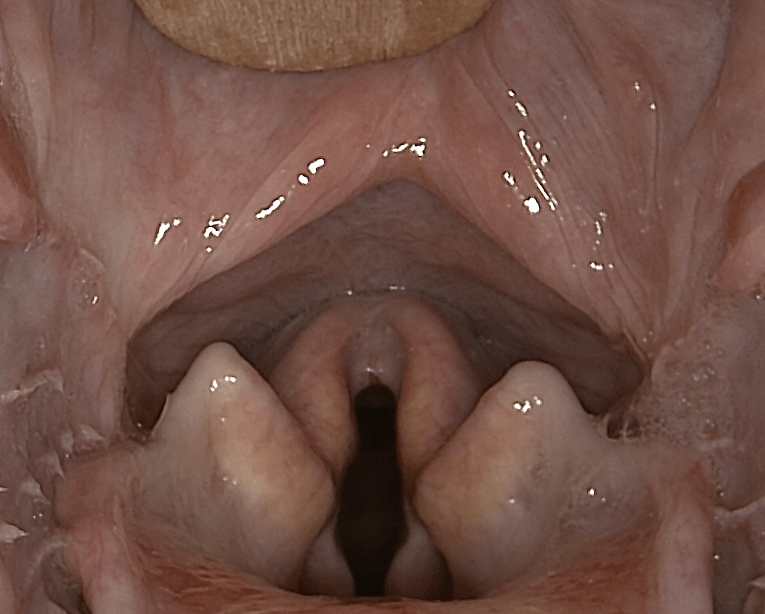

- Laryngoscopie : Cette procédure, réalisée sous anesthésie, permet une visualisation directe du larynx. Le vétérinaire peut observer le mouvement (ou l'absence de mouvement) des cordes vocales pendant la respiration.

Endoscopie du larynx: vue pré et post opératoire